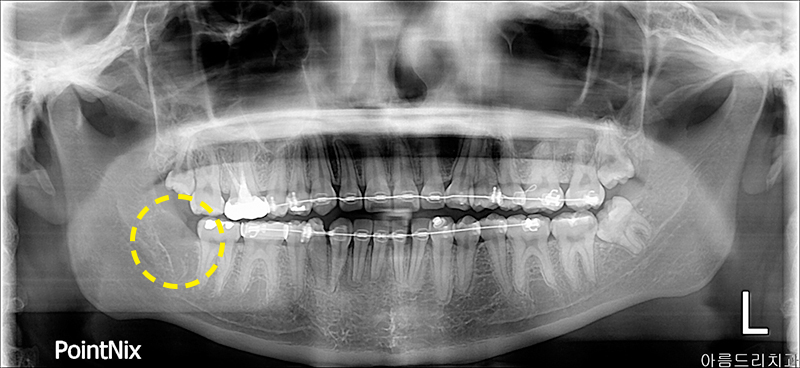

환자분께서는 사랑니 중에서도 난이도가 높은 매복사랑니발치의 케이스였는데요.

매복사랑니란 말그대로 사랑니가 잇몸에 매복 된 상태를 뜻하며 그 각도나 매복된 정도에 따라 다르게 분류되고 치료방법 또한 다르죠.

사진을 보면 우측과 좌측에 매복사랑니가 있는 모습을 확인하실 수 있으실텐데요.

우측에 있는 사랑니와 인접한 치아에 충치가 발생하여 통증이 심해 발치를 원하셨습니다.

파노라마 사진에서도 확인해 보실수 있듯이 매복사랑니발치 케이스인 것을 확인할 수 있었고 육안으로 보기에도 치아가 거의 보이 지 않았으며 더 중요한것은 하악의 사랑니는 설신경과 하치조신경이 지나가기 때문에 매우 신경써서 발치를 진행해야만 합니다.

환자분께서는 얼마 지나지 않아 회사에서 출장 스케쥴이 있으셔서 당일 발치를 원하셨고 아름드리치과의 정밀한 CT촬영과 3차원분석 을 통해 당일 매복사랑니발치를 진행하였어요.

그나마 참 다행이었던 것이 완전매복발치의 케이스는 아니셨기 때문에 잇몸을 절개하고 비교적으로 쉽게 발치를 할 수 있었답니다.